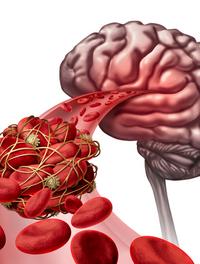

Dans l’accident vasculaire cérébral (AVC) aigu, le premier traitement efficace en termes de reperfusion d’une occlusion d’une artère [...]